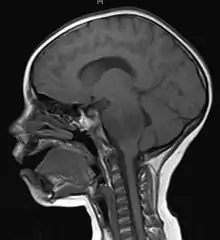

| Brain metastasis in the right cerebral hemisphere from lung cancer, shown on magnetic resonance imaging | |